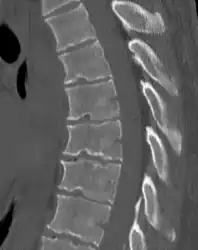

Diagnosis is typically by medical imaging. The degree of kyphosis can be measured by Cobb's angle and sagittal balance.

Scheuermann's disease on lateral CT of the T spine